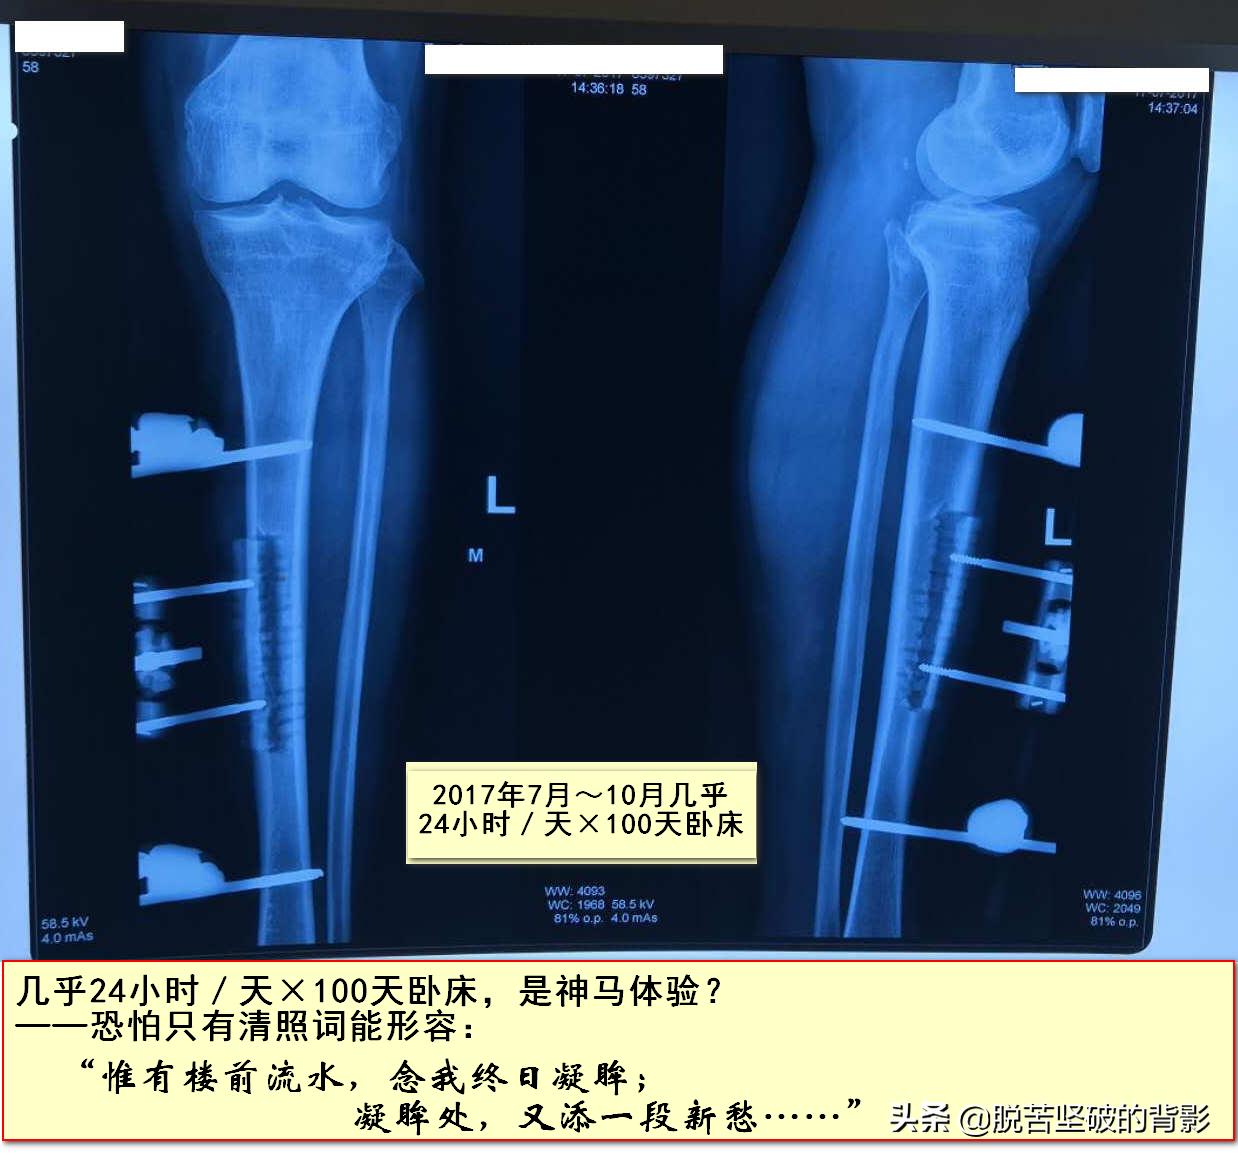

他于2017年7月接受了一种高端手术——胫骨横向骨搬移术——把正常骨头切开搬移!

◎术后必须几乎24小时卧床!

◎合计卧床:几乎24小时/天×100天!

——这是什么样的体验?

——恐怕只有清照词能形容吧:

“惟有楼前流水,念我终日凝眸,

凝眸处,又添一段新愁……”